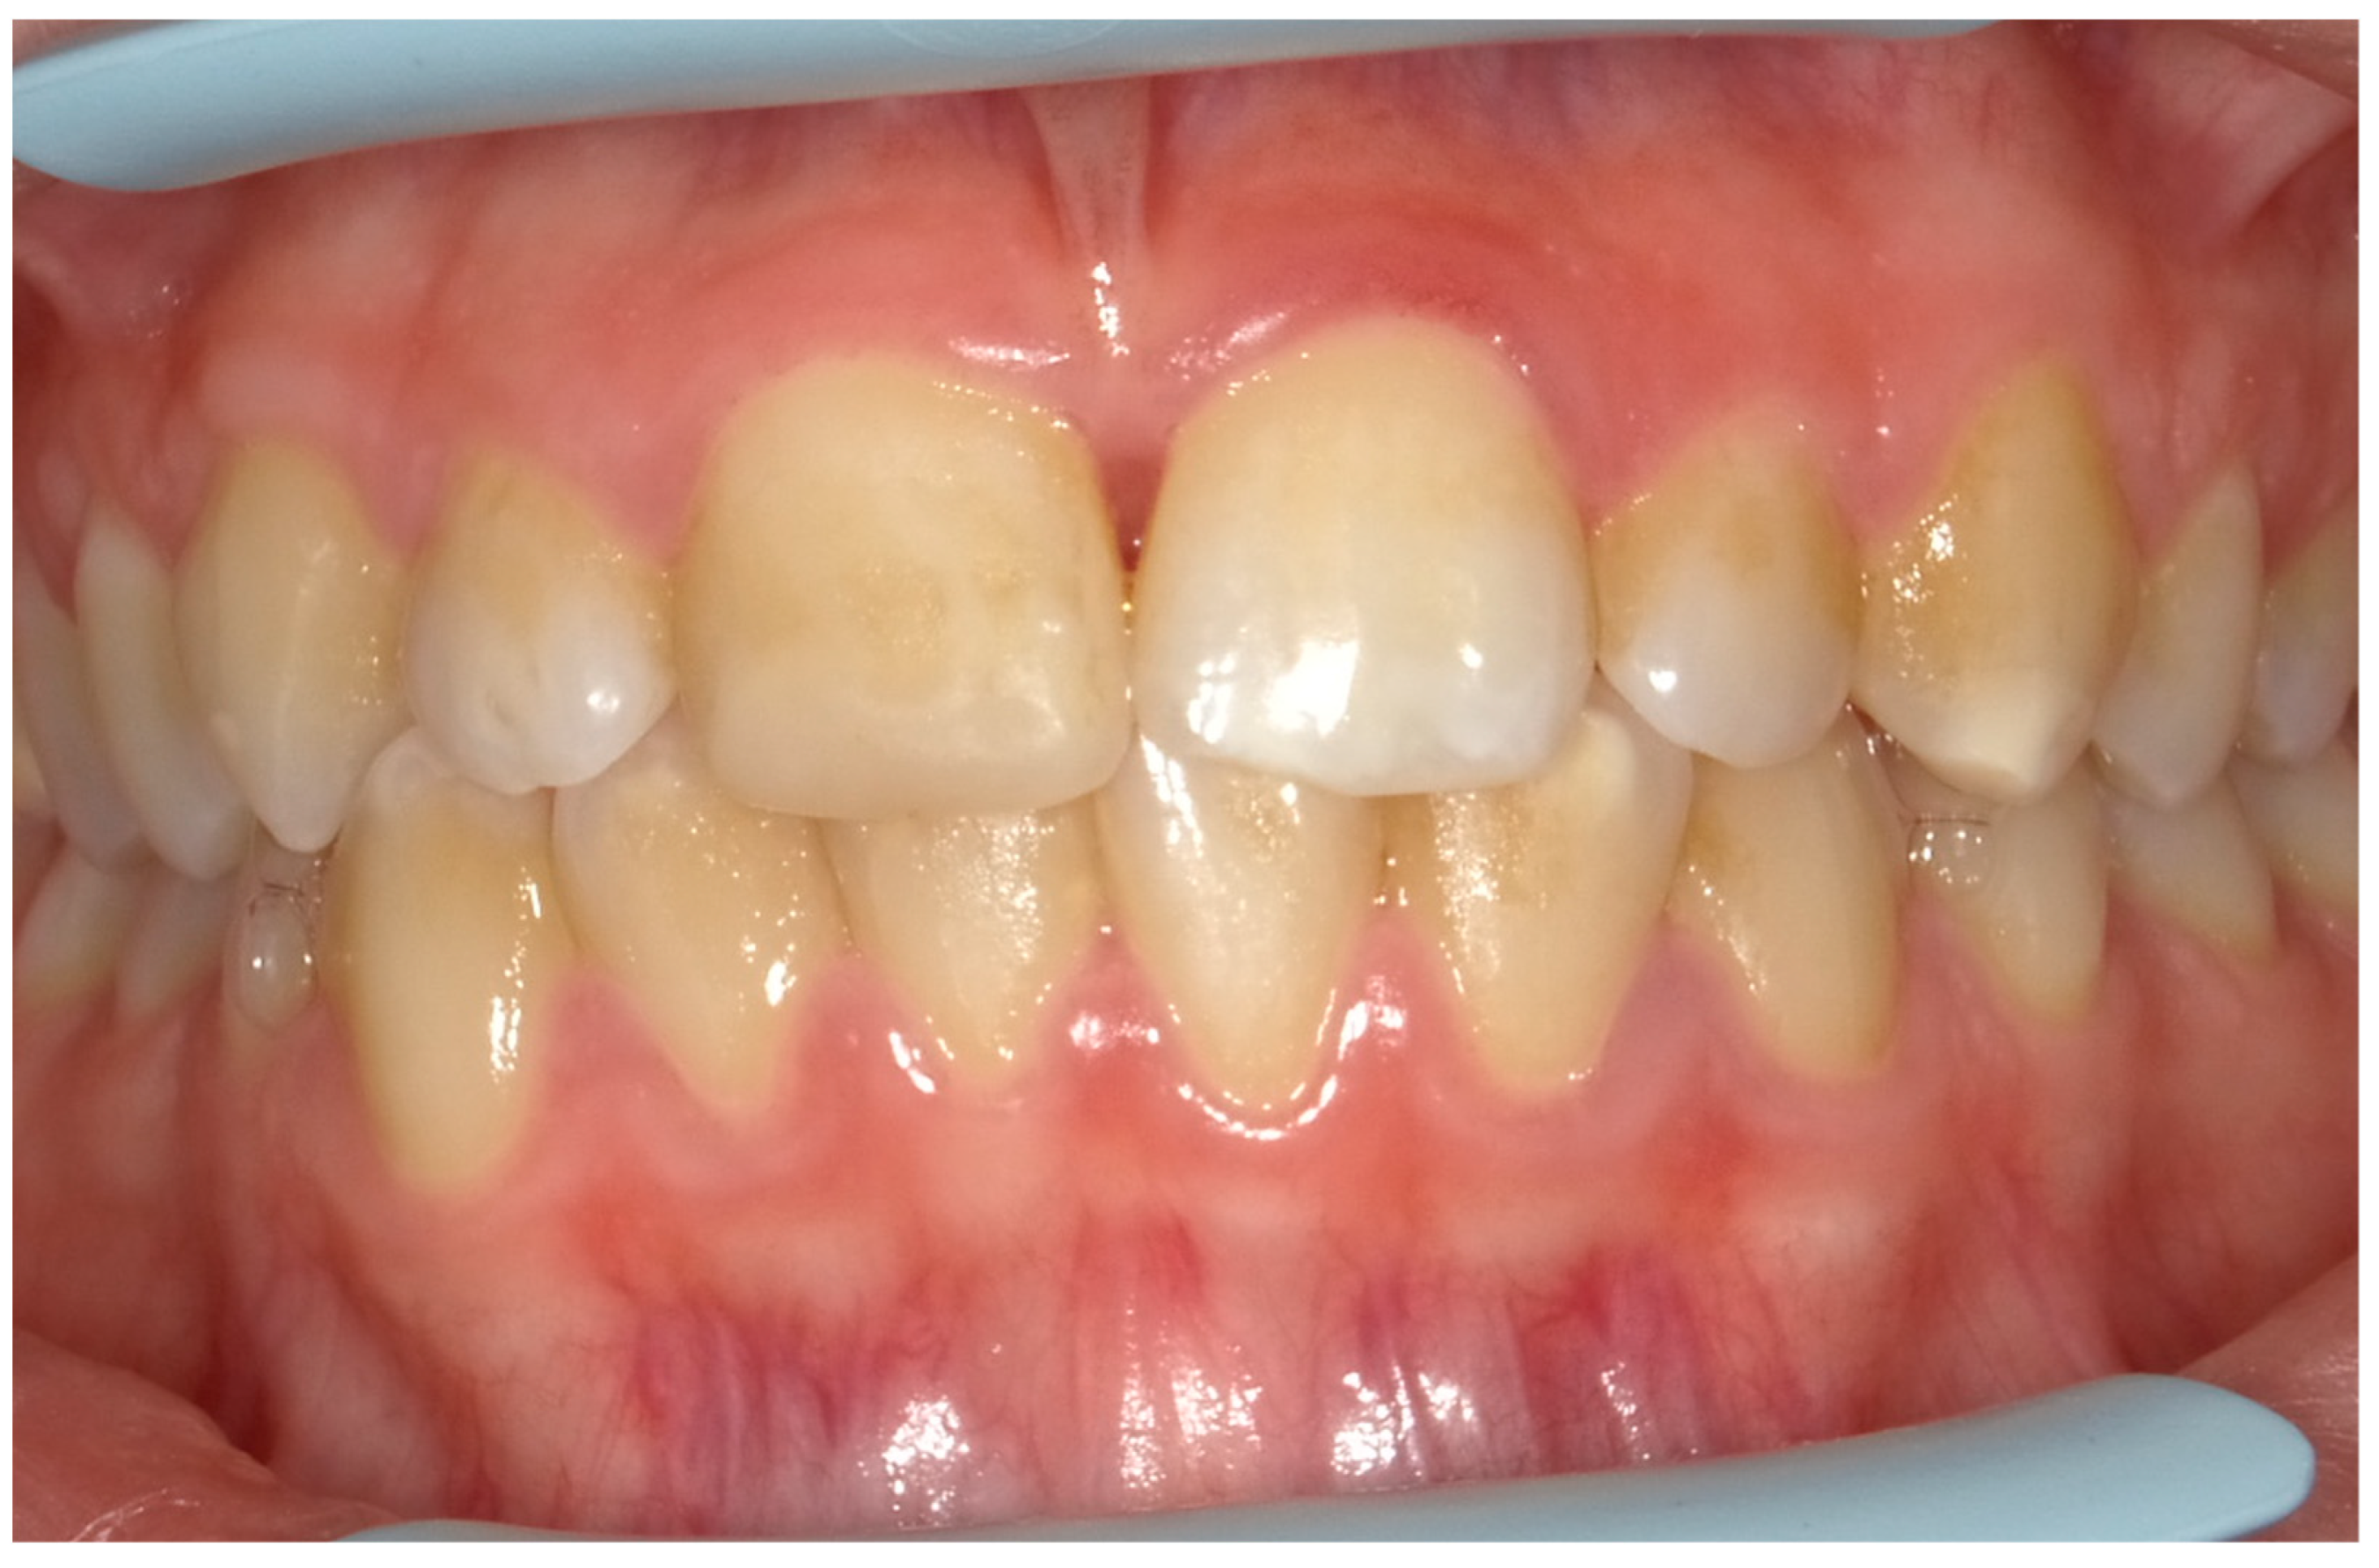

4.1. Case 1